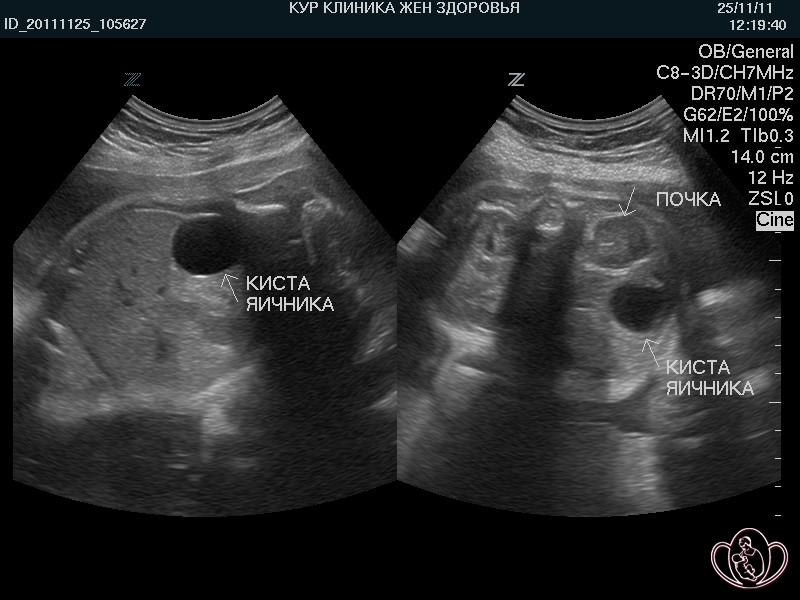

УЗИ ОМТ: (Рис.1): тело матки в anteflexio, размерами 60х45х51 мм, контур ровный, структура однородная.

М-эхо: 17 мм, полость матки расширена до 8 мм за счет анэхогенного содержимого. Шейка матки однородная, не расширена. Правый яичник: достоверно не лоцируется, в проекции правого яичника анэхогенное образование 65х55 мм. Левый яичник: достоверно не лоцируется, в проекции расположения левого яичника лоцируется анэхогенное образование 26х23 мм с толщиной стенки до 6 мм, без достоверного кровотока. Свободная жидкость в малом тазу визуализируется до 13 мм в подматочном пространстве, в области дна до 15 мм с гиперэхогенными перетяжками.

Заключение: УЗ признаки структурных изменений эндометрия, кисты правого яичника, образования левого яичника. Свободной жидкости в малом тазу.

Рисунок 1 - Ультразвуковое исследование органов малого таза